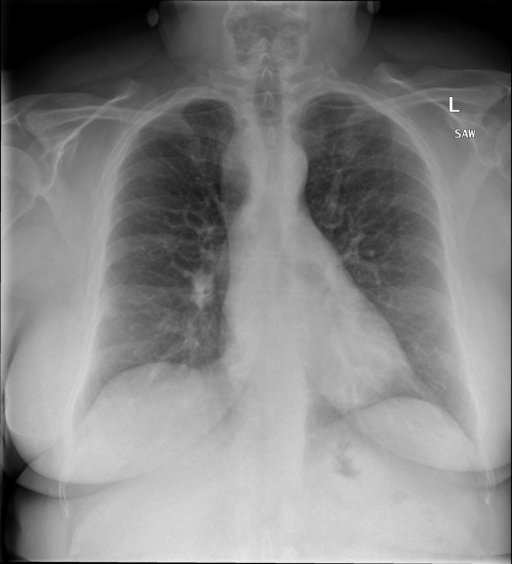

|X光影像|诊疗报告(医生)|

|:-|:-|

||右侧主动脉突出观察到。心脏大小正常。胸部未发现明显的肺气肿、胸膜积液或可疑的肺部病变。报告指出已知右侧主动脉情况正常。|

```bash

>> X光影像路径:./data/Xray/861_1.png

>> 用户:这是一张什么图?

>> XrayGLM:这张图片显示的是一张肺部检查的X光片。

>> 用户:请描述这张胸部X光片的诊断结果

>> XrayGLM:心脏大小正常,肺部清晰。没有急性心肺疾病的证据。

>> 用户:是否存在肺气肿?

>> XrayGLM:没有肺气肿。心脏大小正常,肺部清晰。没有发现急性心肺疾病的证据。

>> 用户:平时饮食该注意什么?

>> XrayGLM:饮食应该健康,均衡。建议增加蛋白质的摄入量,因为蛋白质有助于维持肌肉和骨骼的健康。多食用蔬菜、水果、全谷物以及健康的脂肪来源如橄榄油、鱼类等可以帮助获得足够的维生素和矿物质。此外,避免过度饮酒或吸烟,这些习惯可能会对心脏健康产生负面影响。

```